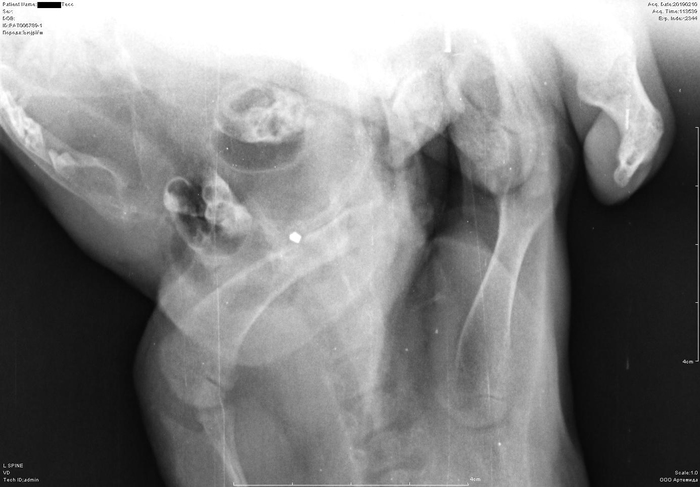

Рентген котенка

Добрый день. Котенок рожден 5 ноября 2018 года, девочка, не привита. Проглистована. Неожиданно в один момент стала припадать на задние ноги. Как бы бережет их и старается не прыгать лишний раз. Свозили два дня назад к ветеринару - всю её прощупал, говорит переломов нет, вывихов тоже. Сделали блокаду ближе в крестцу новокаина, чтобы снять симптомы. Прописал кальций в таблетках Ексел. Сейчас всё примерно так же - лапки задние бережет, но стала по активнее. Прошу специалистов, если такие тут бывают, оценить снимки, т.к. врач ещё кое-что сказал и хотелось бы услышать ваше мнение. Скан расшифровки и д/з потом приложу.

Боковая проекция